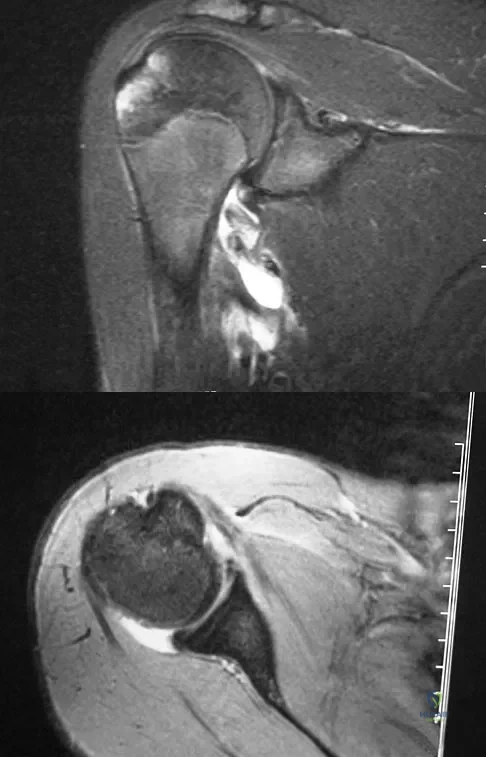

A 37-year-old man with a history of congenital flatfoot reports worsening pain on the medial aspect of his ankle for the past year. The pain is worse with weight bearing and is better with rest and the use of an ankle brace. What findings are shown on the MRI scans shown in Figures 18a through 18c?

Explanation